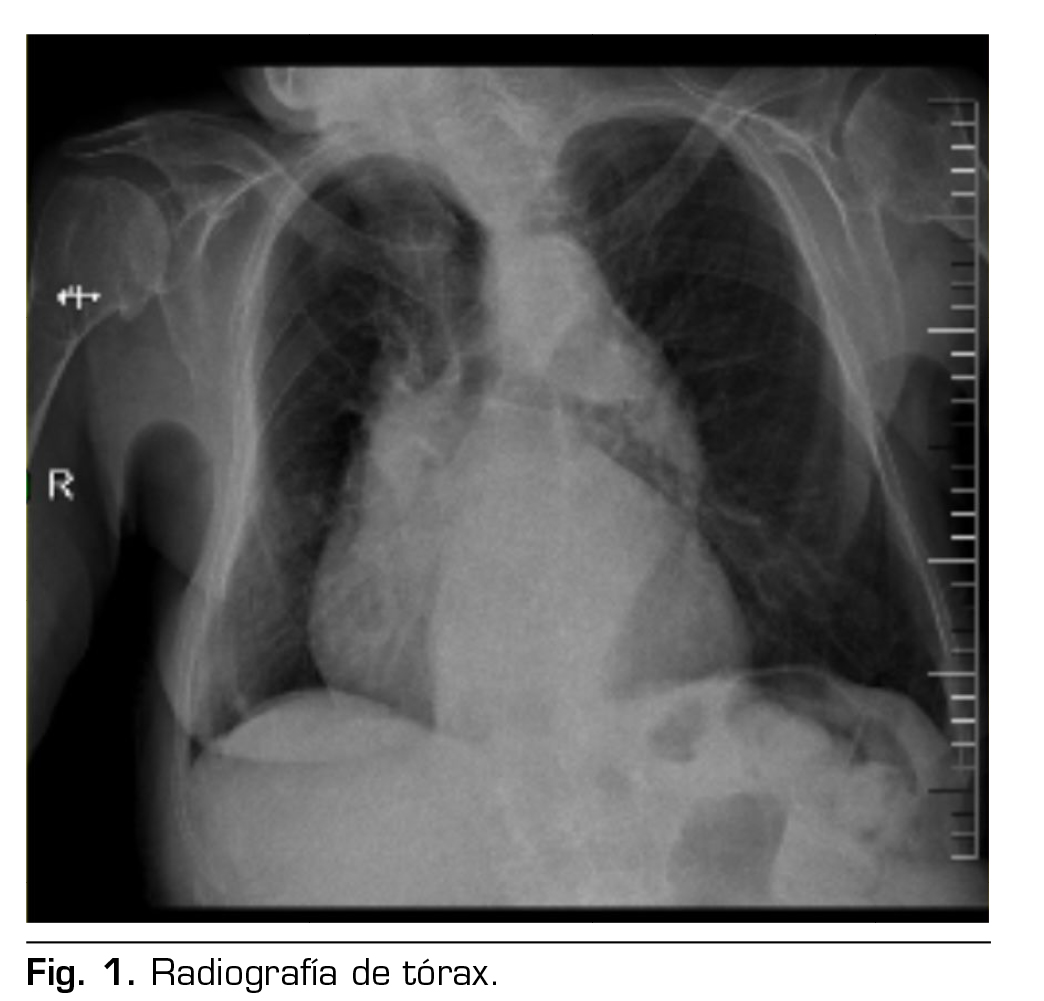

Figura 2

Presentación de caso: Presentamos el caso clínico de un paciente adulto mayor de 88 años ASA III, sometido a una hernioplastia inguinal electiva, bajo anestesia regional: bloqueo II/IH bajo guía ecográfica más sedación, manejo analgésico complementario con paracetamol y antinflamatorios, alta de cirugía médica ambulatoria a su domicilio y control postoperatorio sin complicaciones.

Case presentation: We present the clinical case of an 88-year-old adult patient ASA III, for elective inguinal hernioplasty, under regional anesthesia: Ilioinguinal-Iliohypogastric block under ultrasound guidance plus sedation, complementary analgesic management with paracetamol and anti-inflammatory drugs, discharge from outpatient surgery to his home and postoperative control without complications.